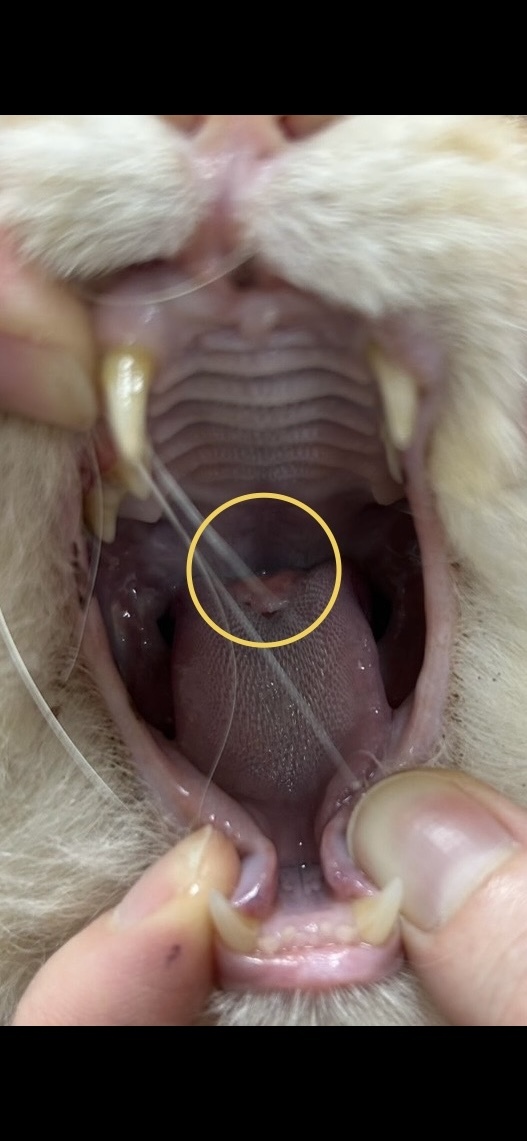

◉舌に腫瘍があります。

多頭現場から最初の初期ケアの病院で舌腫瘍が見つかりました。

預かりメンバー宅に来てから最初に行った病院では舌の奥のど真ん中にあるので、手術は難しいとの診断でした。

セカンドオピニオンでは、キレイに取れるかはわからないができるところまで手術はできるとの診断を頂きました。

1番最後のページに腫瘍の画像を貼ります。

苦手な方は飛ばして下さい。

ハルくんの腫瘍です。